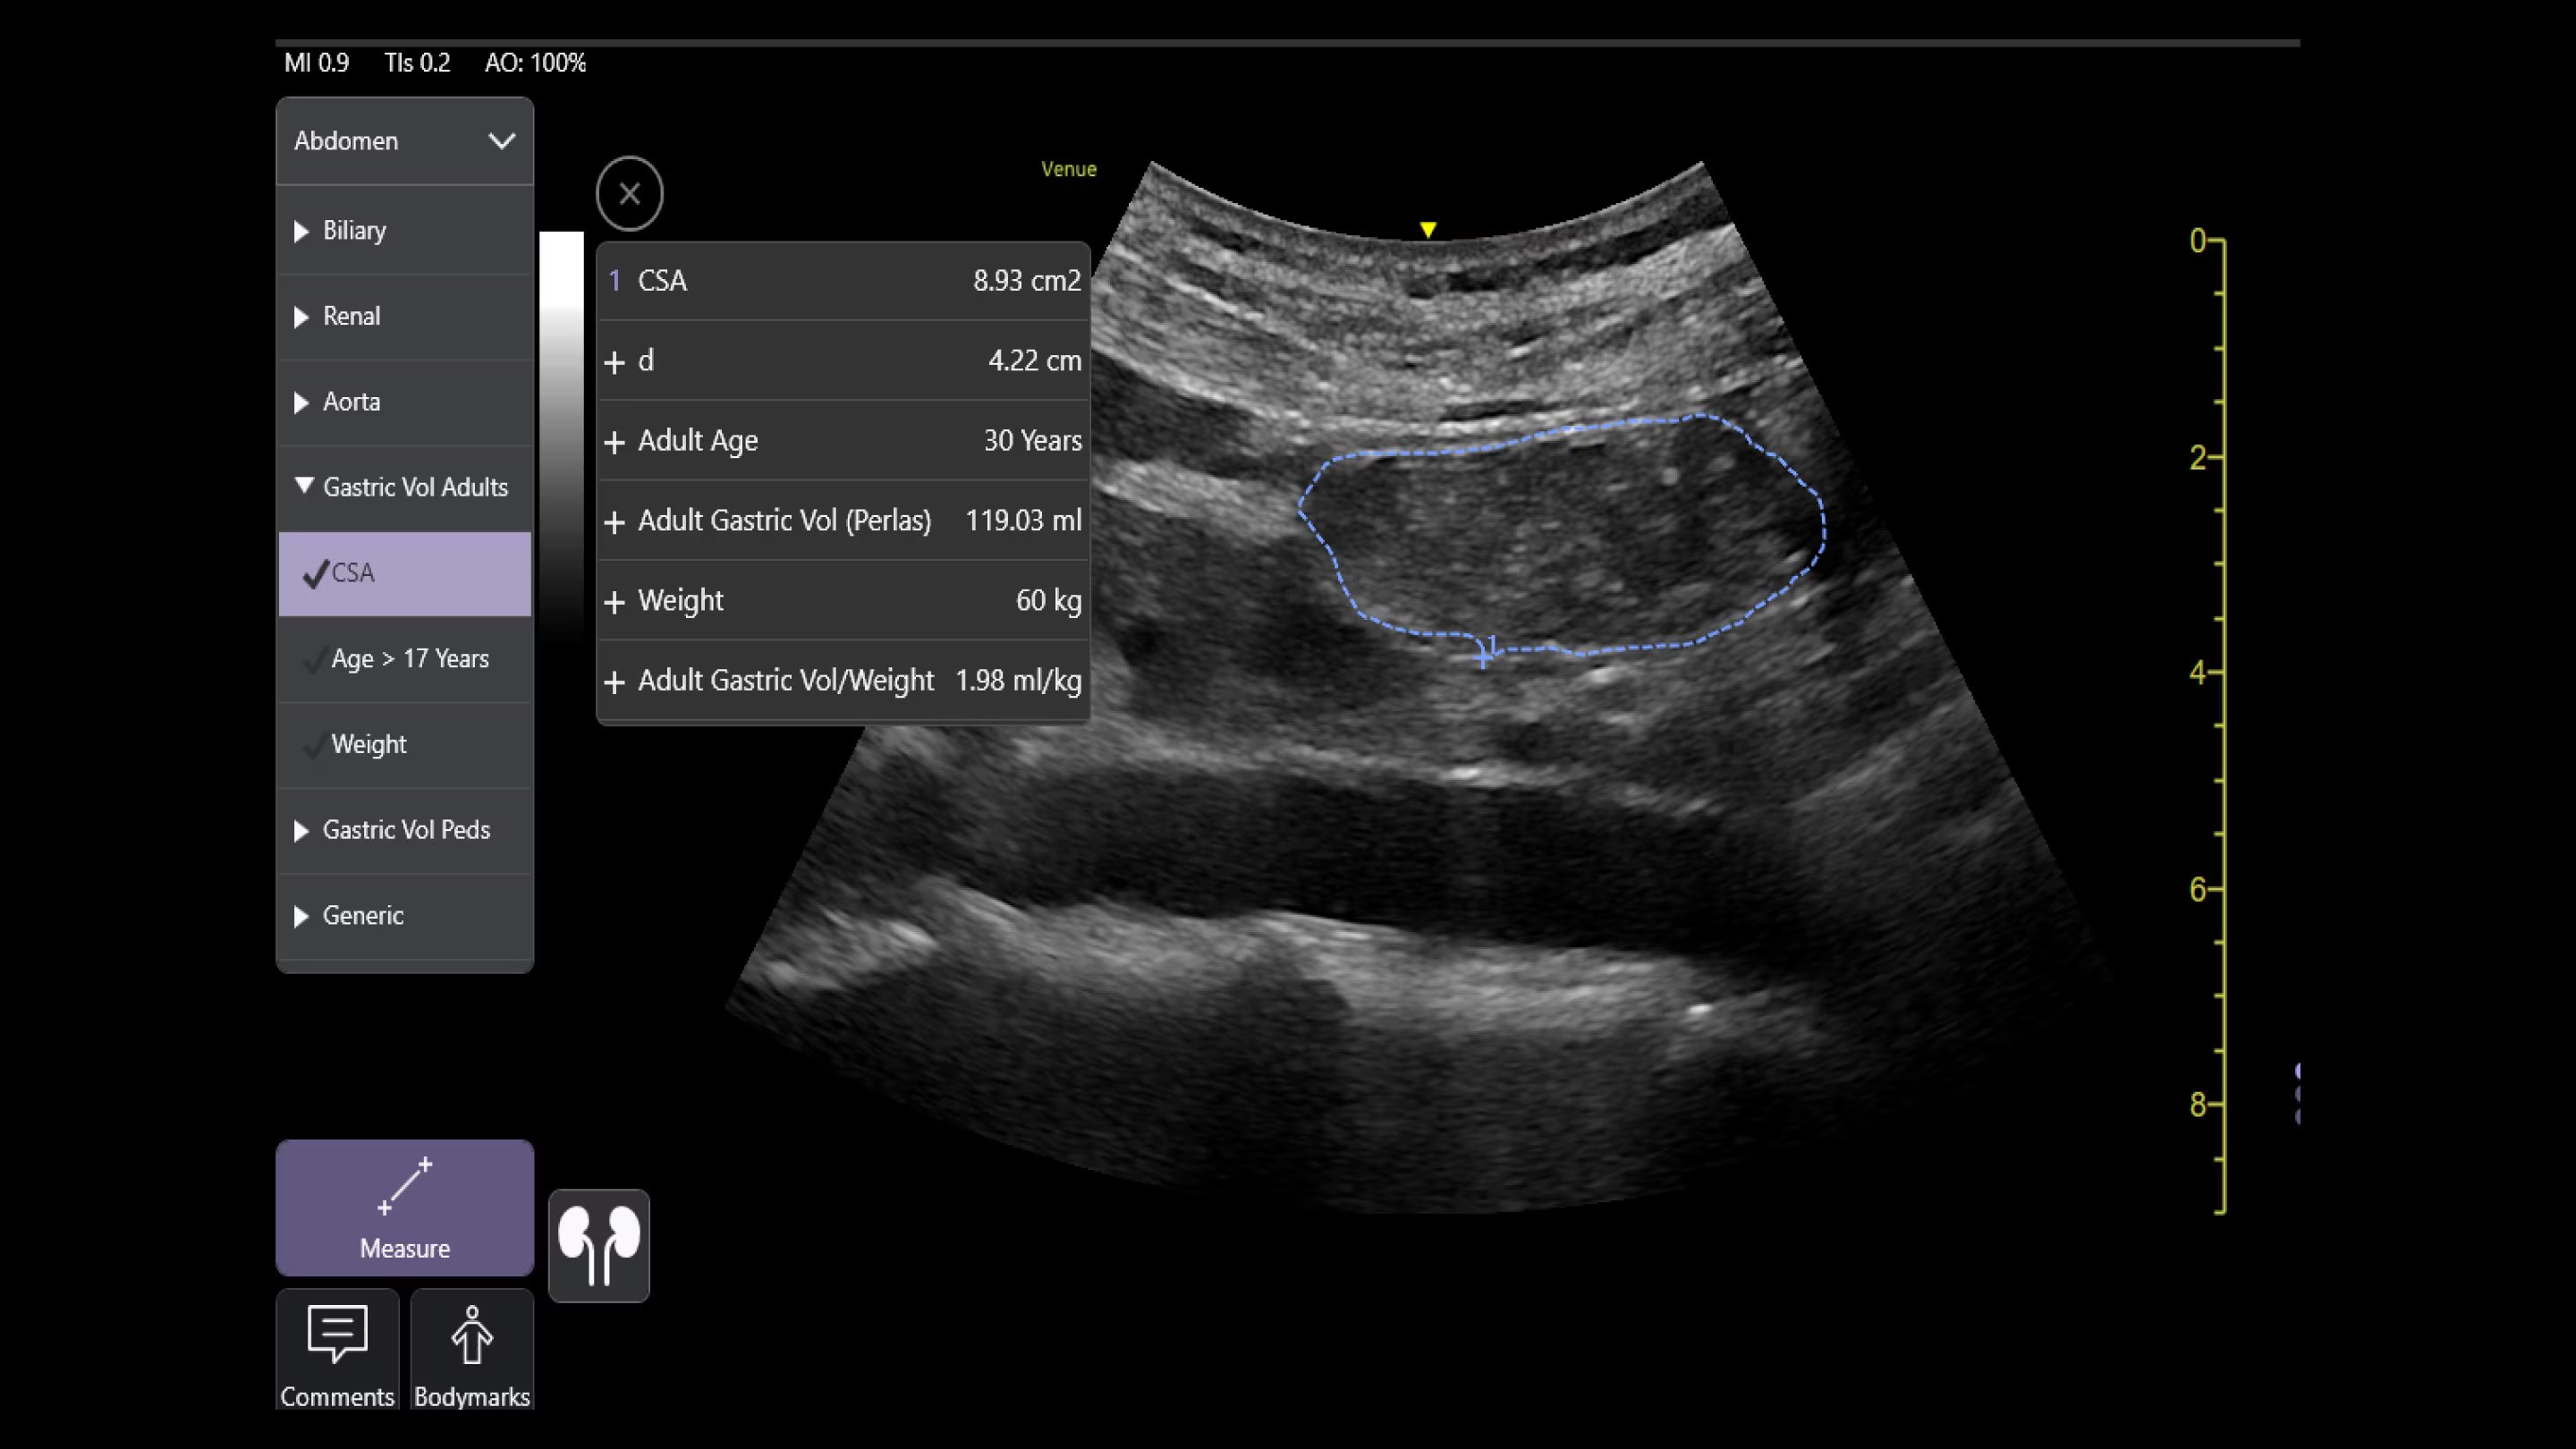

Automated tools

Simplify your workflow with AI-enabled clinical tools.

Helping drive consistency from user to user (whether one is an ultrasound novice or expert), Venue Fit features AI-enabled resources that help clinicians work smarter and more efficiently. Utilizing proprietary algorithms, we synthesize data from numerous patients to ensure accurate calculations for clinical confidence.